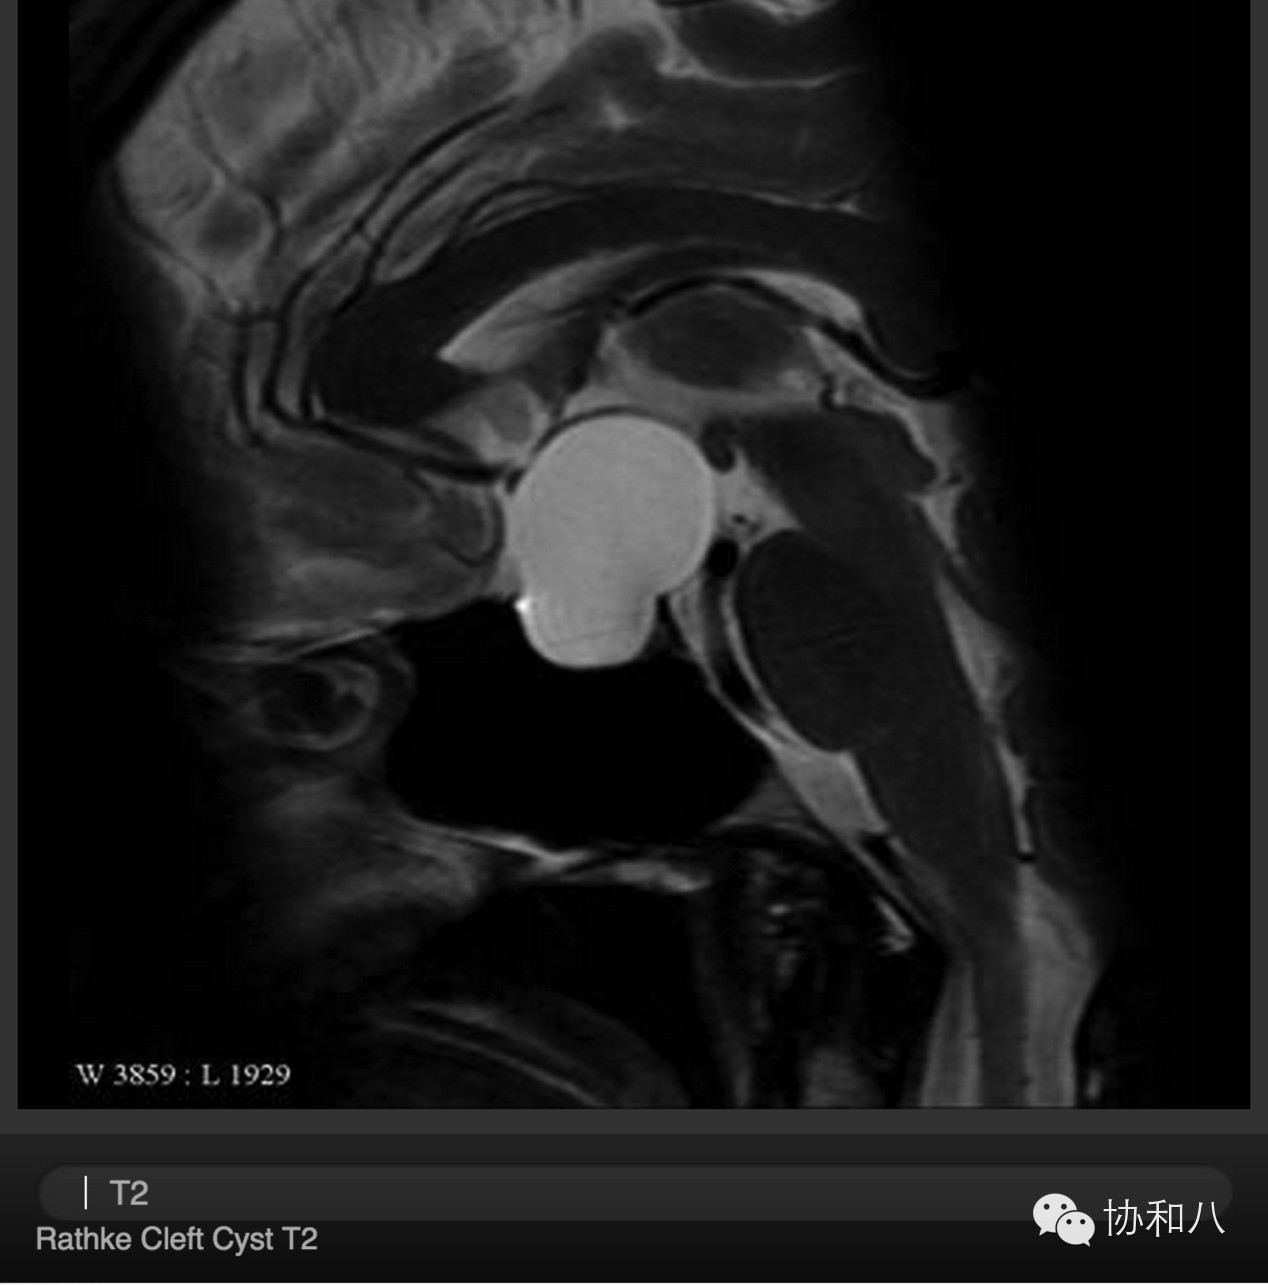

(3)Rathke裂囊肿

• 通常没有临床症状;

• 不表现为实性肿物;

• 球形。

下图:(矢状位MRI T2WI)鞍区及鞍上囊性占位。